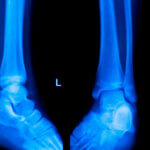

Erfolgreiche Operation dank 3D-Druck: Ein in den USA ansässiger Patient hat Dank medizinischem 3D-Druck und der Fachkompetenz von Dr. Lauren Geaney, einer Fuß- und Sprunggelenkchirurgin am UConn Health’s Musculoskeletal Institute, ein neues Knöchelimplantat erhalten. Nach einem schweren Knöcheltrauma im Jahr 2021 suchte Patientin Lori Cannon nach Möglichkeiten, ihre Mobilität wiederzuerlangen. „The Day“ hat darüber berichtet (dort finden Sie auch Bilder).

Dieses innovative Implantat, zusammengesetzt aus Titan und Polyethylen und beschichtet mit Titannitrid, versprach eine verbesserte Langlebigkeit und Funktion. Nach sorgfältiger Überlegung und Planung wurde das 3D-Druck-Implantat in einem fünfstündigen chirurgischen Eingriff eingesetzt. Die Ergebnisse waren beeindruckend: Cannons Bewegungsfreiheit hat sich erheblich verbessert und ihre Schmerzen sind deutlich zurückgegangen.